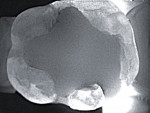

Another promising imaging technology that has come to market over the last few years is the CariVu (Dexis). It uses a wavelength of light that facilitates near-infrared transillumination to detect caries on both the occlusal and proximal surfaces as well as cracks (Figure 5 and Figure 6). At this relatively long wavelength, enamel becomes transparent to photons, whereas porous lesions trap and absorb the photons. This phenomenon causes any lesions to appear dark. This technology is especially helpful at diagnosing approximal caries without the need for ionizing radiation. When teeth are illuminated and imaged from the occlusal surface, approximal caries will clearly show up as dark areas extending from the approximal surface towards the dentin. A clinician can then share this image with the patient to easily and clearly show the progression of disease instead of trying to explain radiolucency on a bitewing radiograph. While this technology does not entirely replace bitewing radiographs, it may minimize the need for radiographs among periodontally stable patients. Recent research suggests that near-infrared transillumination is an effective method for diagnosing lesions involving only the enamel as well as those involving the enamel and dentin.8 This technology has also been helpful in visualizing cracks on teeth. Cracks prevent light transmission and will appear as dark spots, alerting the clinician to potentially significant issues and allowing for more conservative treatment.